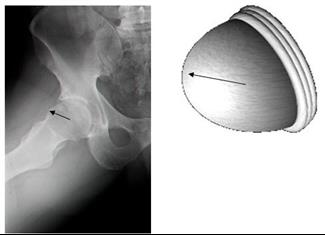

מפרק הירך הוא המעוז האחרון שנכבש על ידי הניתוחים הארתרוסקופים. הברך, הקרסול, הכתפיים, מרפק ושורש כף היד - מנותחים ב... לכתבה המלאה

ארתרוסקופיה של הירך, ניתוח המתבצע באמצעות מצלמה וכלים זעירים המוחדרים אל מפרק הירך ומחליפים ניתוח "קונבנציונלי", מא... לכתבה המלאה